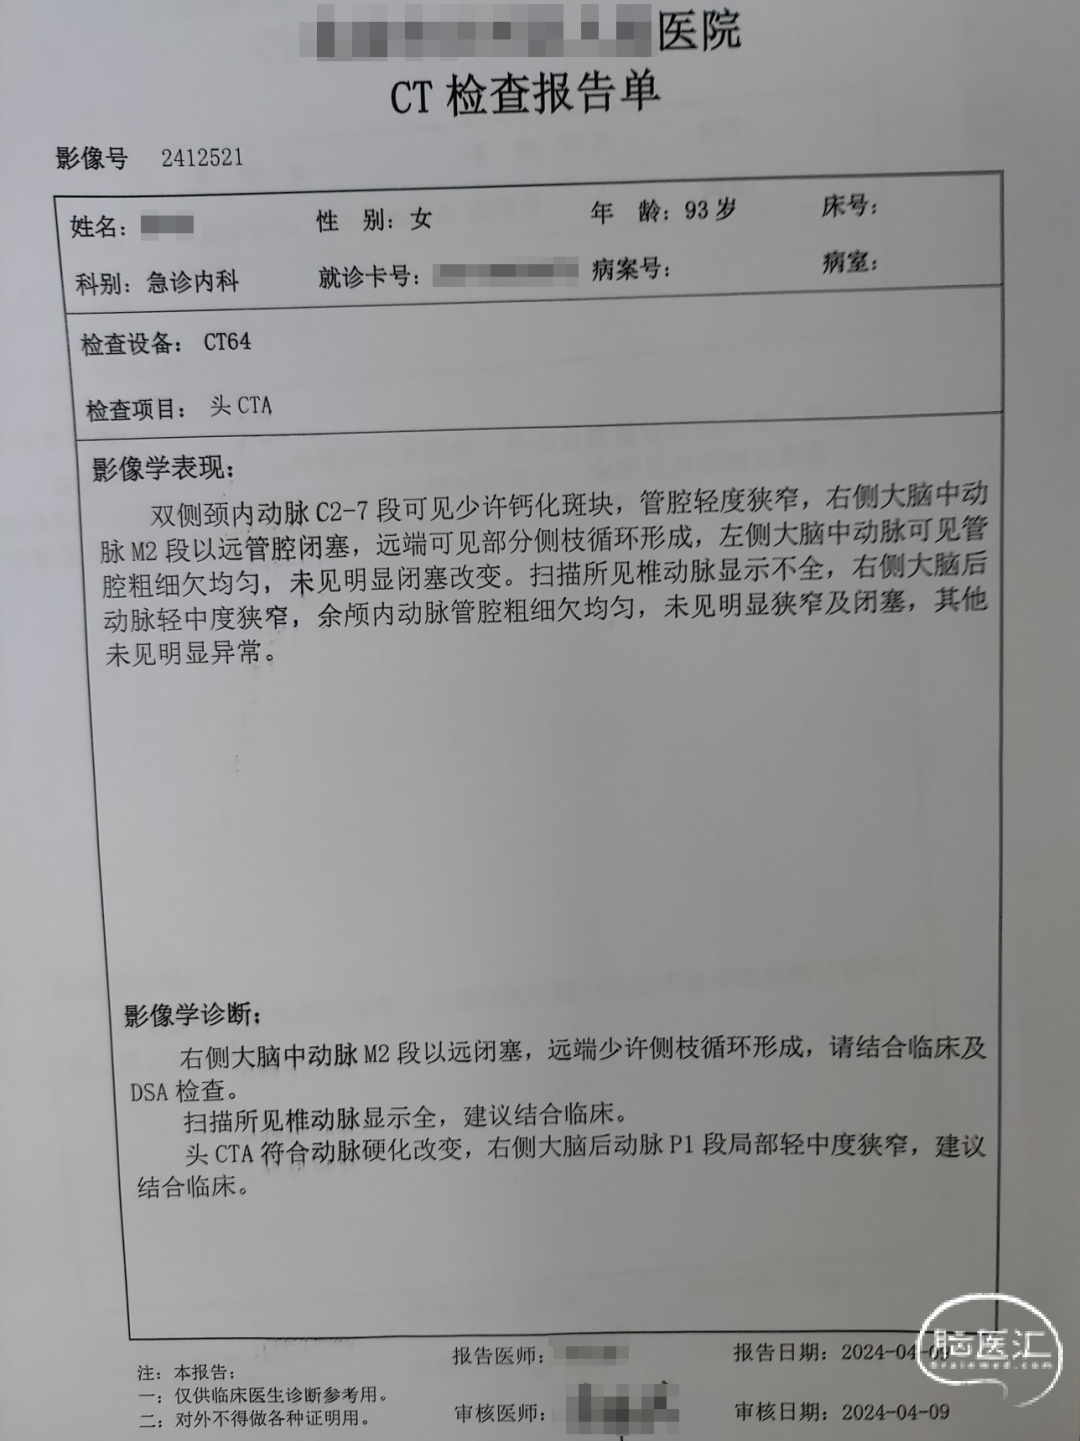

➤术前检查(2024.4.9,外院)

影像学诊断:右侧大脑中动脉M2段以远闭塞。

➤取栓前造影(2024.4.9,16:03:15)

造影显示:右大脑中动脉M1段闭塞,血流0级,右大脑前动脉通过软脑膜动脉部分代偿右大脑中动脉,结合临床,考虑右大脑中动脉起始部闭塞处为责任病灶,决定行动脉取栓治疗。